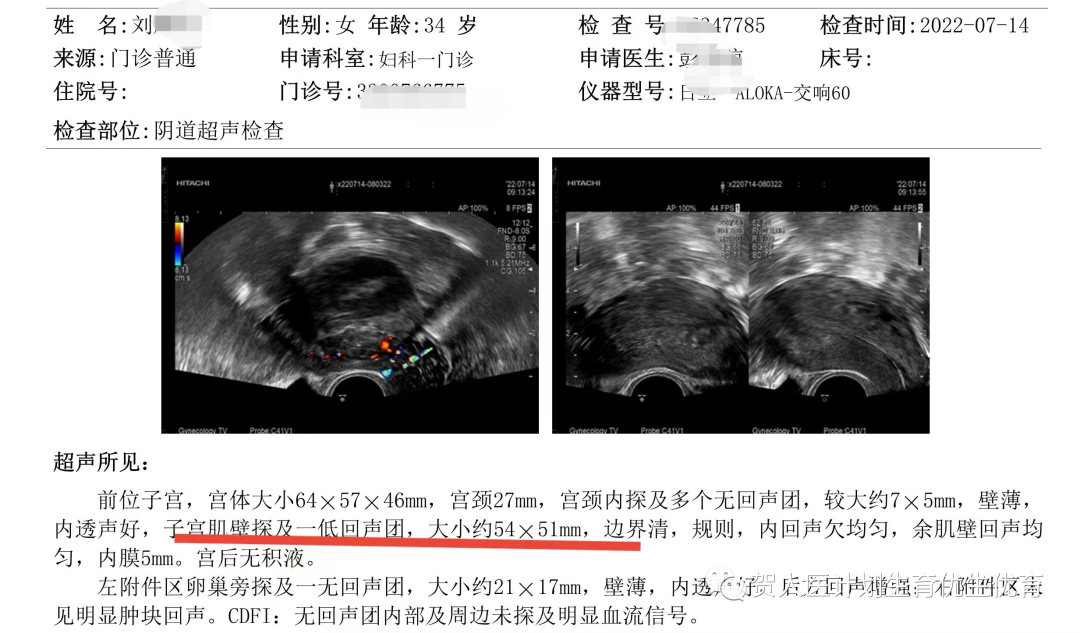

患者术前超声检查

案例一:患者刘某青,2021年7月因“发现子宫肌瘤3年,月经增多4个月”来我院就诊。妇科检查发现子宫增大如妊娠2月大小,B超提示子宫占位,子宫肌壁探及79*66mm低回声团,肿瘤压迫子宫内膜,考虑子宫肌瘤。诊断子宫肌瘤。入院后排除禁忌后行子宫肌瘤微波消融术,术后顺利出院,无不良反应。今年7月回访患者,无不适症状,月经量正常,B超提示子宫肌壁低回声团54*51mm,体积较前缩小达62%。